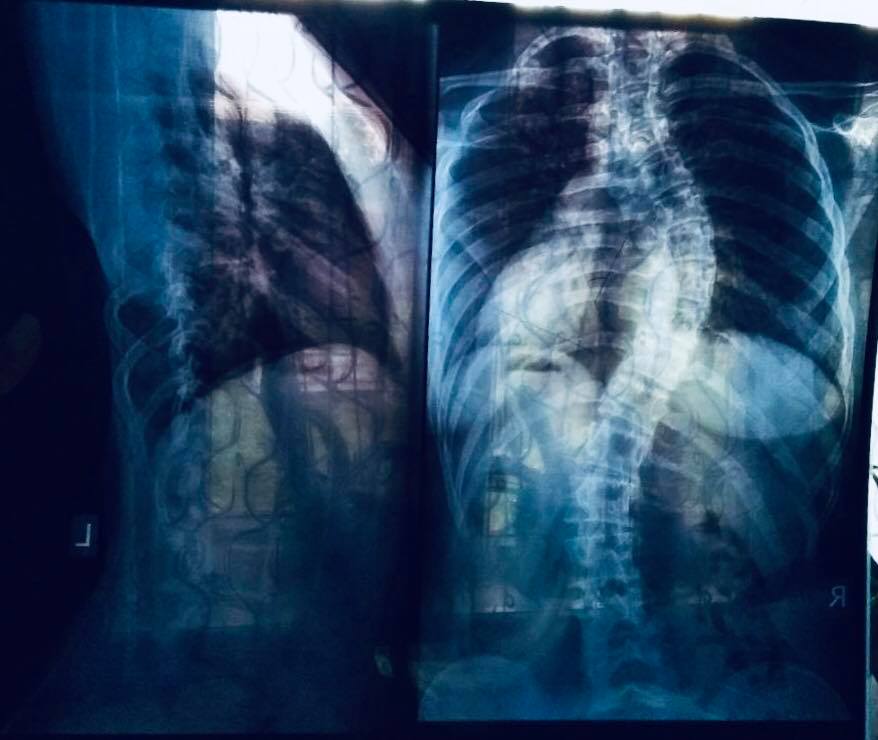

Під час звичайного профогляду в квітні цього року в сільській амбулаторії фельдшер помітив, що хребет дівчинки надзвичайно швидко викривився. Вже через декілька місяців їй поставили діагноз сколіоз IV ступеню.

Мама Світлана пройшла з Альоною безліч спеціалістів. Проте хребет за півроку лікувань вже викривило на понад 50 градусів.